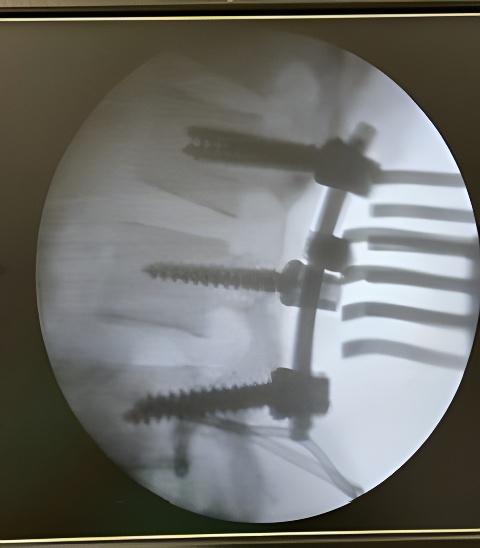

Cirurgia de columna

Cirurgia endoscòpica de columna